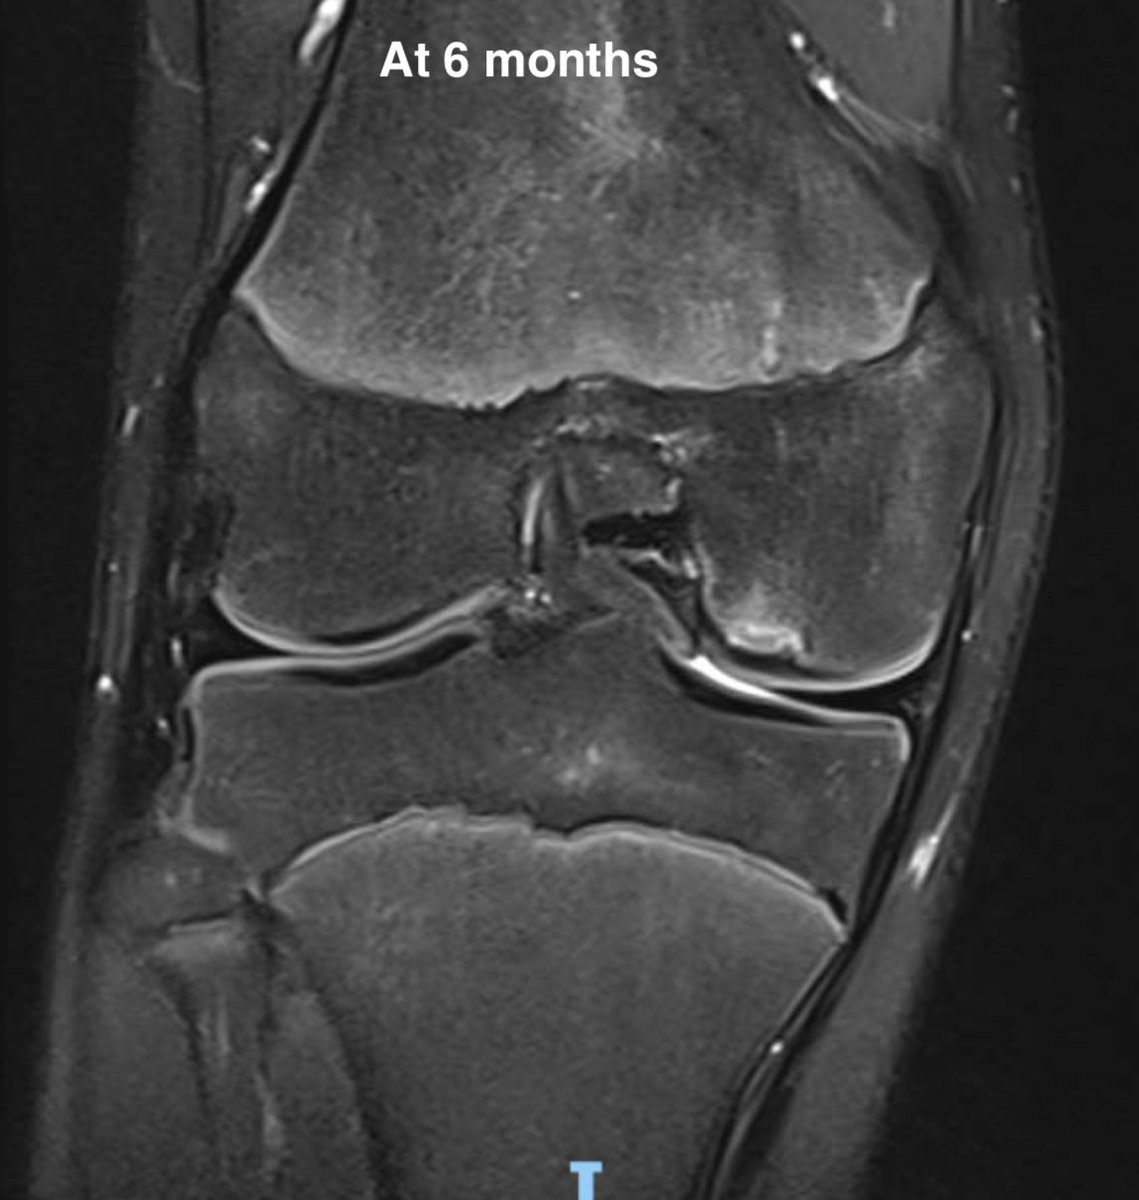

8. Subchondral insufficiency fracture (ex SONK!)

Older demographic, poor bone health risk factors, meds

? Hx of trivial injury eg step off steep kerb, turnstile

Typical to have meniscal tear associated

Effusion, deep bony pain on WB / impact